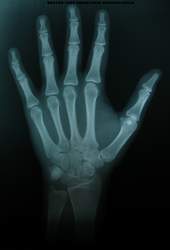

O que é radiografia?

A radiografia é o registro

fotográfico de uma imagem produzida pela passagem de uma fonte de raios X

através de um objeto.